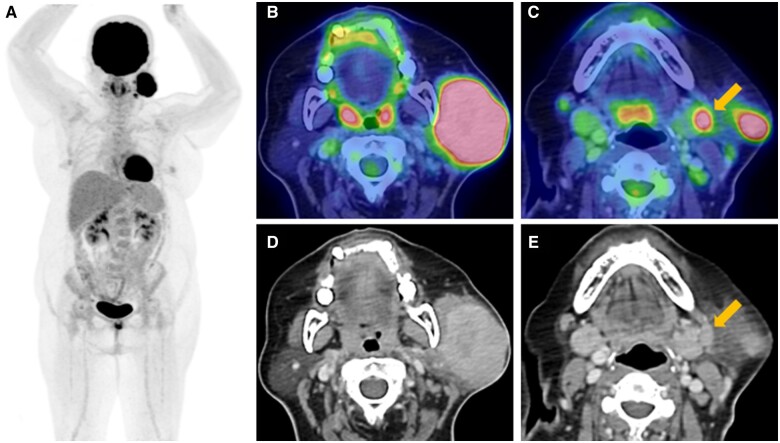

The authors present the case of a 59-year-old lady diagnosed with lymphoepithelial carcinoma (LEC) of the left parotid gland. The primary tumour was identified using contrast-enhanced CT, and diagnosis was confirmed via fine needle aspiration cytology and immunohistochemistry. Staging using fluorine-18 fluorodeoxyglucose PET CT revealed regional nodal metastases, while no distant metastasis was evident. Following radical radiotherapy, a favourable locoregional response was observed on MRI, yet the patient's plasma Epstein-Barr virus load continued to rise. Given her primary tumour's somatostatin receptor type 2 (SSTR2) positivity, gallium-68 DOTA-[Tyr3] octreotate PET CT (68Ga-DOTATATE PET CT) was performed, revealing multiple distant metastases with DOTATATE avidity. Despite attempts at palliative chemotherapy and immunotherapy, disease progression led to the decision for the best supportive care. The unique presentation of metastatic LEC on 68Ga-DOTATATE PET CT suggests a potential role for SSTR2-targeted imaging in diagnosis and management.